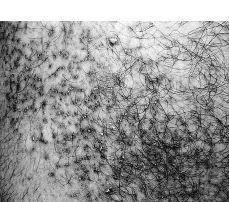

Con el diagnóstico de QLC se valoró iniciar tratamiento con acitretino, pero ante la elevación registrada de las transaminasas y la duda de un cumplimiento responsable por el paciente se prefirió el tratamiento con calcipotriol pomada aplicada dos veces al día. Fue revisado a los 2 meses, observándose una lenta mejoría clínica de las lesiones, con aplanamiento y disminución del eritema (Fig. 4).

FIG.4.--Aspecto clínico de las lesiones del brazo derecho tras 8 semanas de tratamiento con calcipotriol tópico.